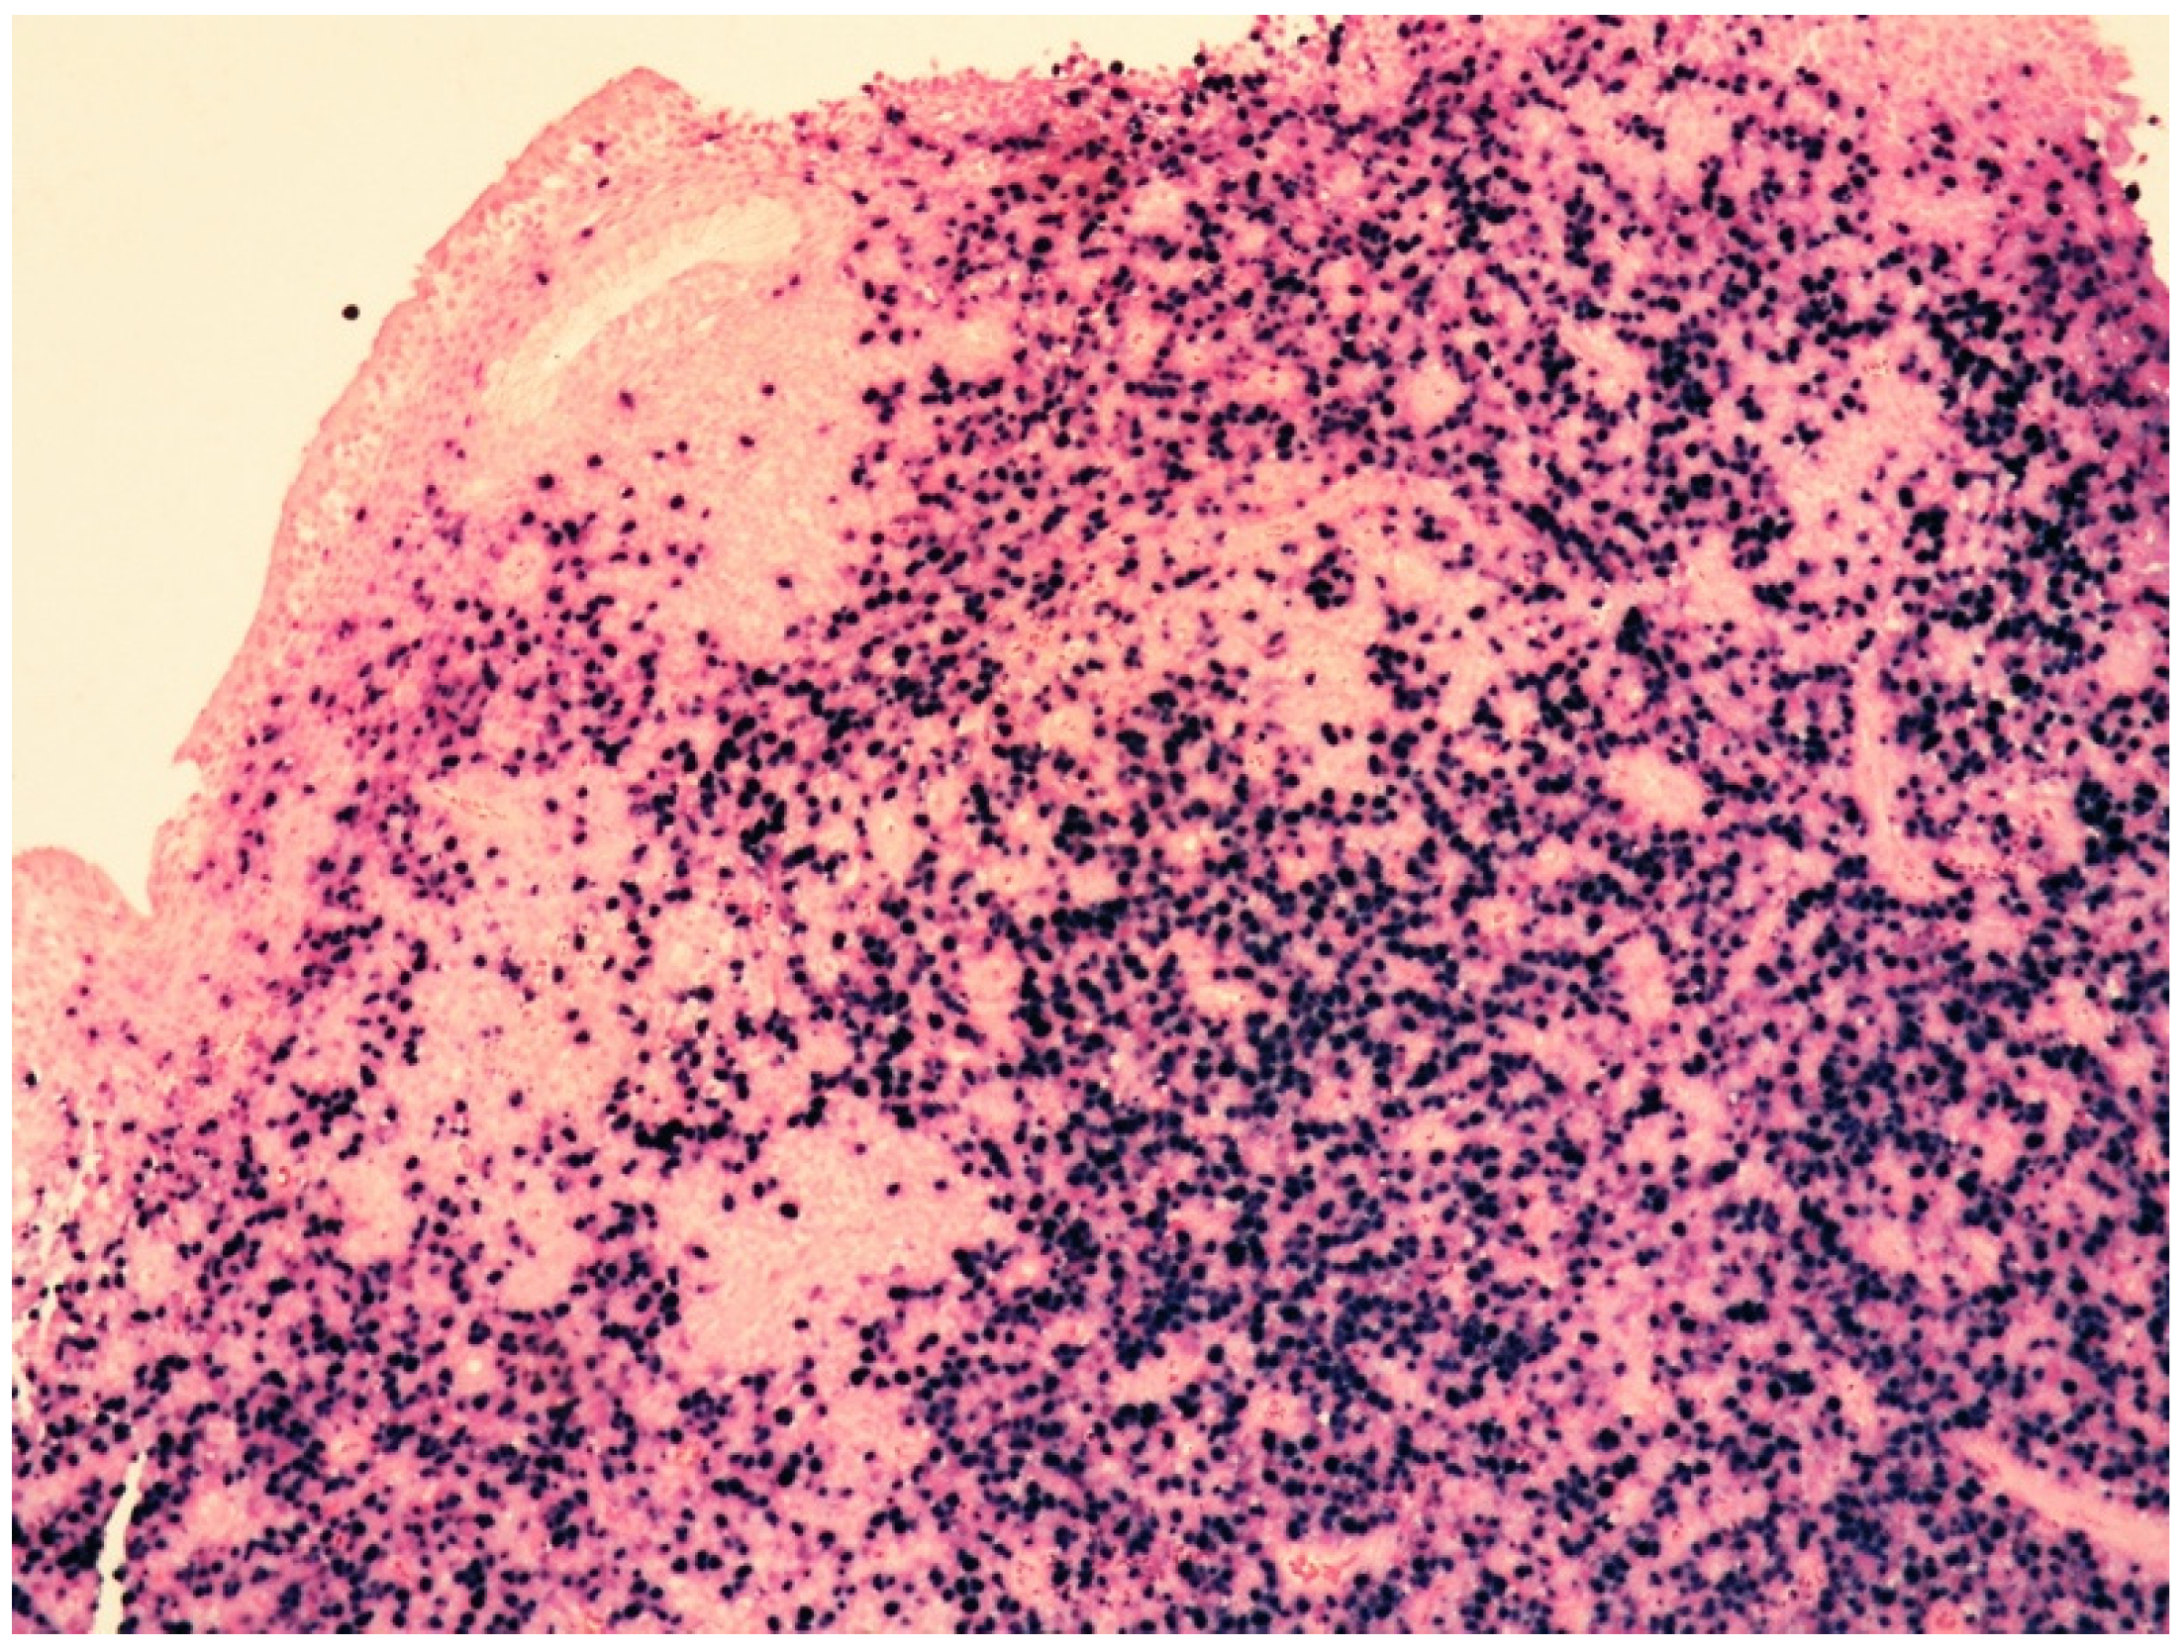

EBER is positive in the majority of viable neoplastic cells (Figure 9).

Figure 9.

Medium-power view showing a diffuse proliferation of EBER-positive cells (in situ hybridization for EBV-encoded RNA, 100× magnification, previously unpublished, original image from S.A.).